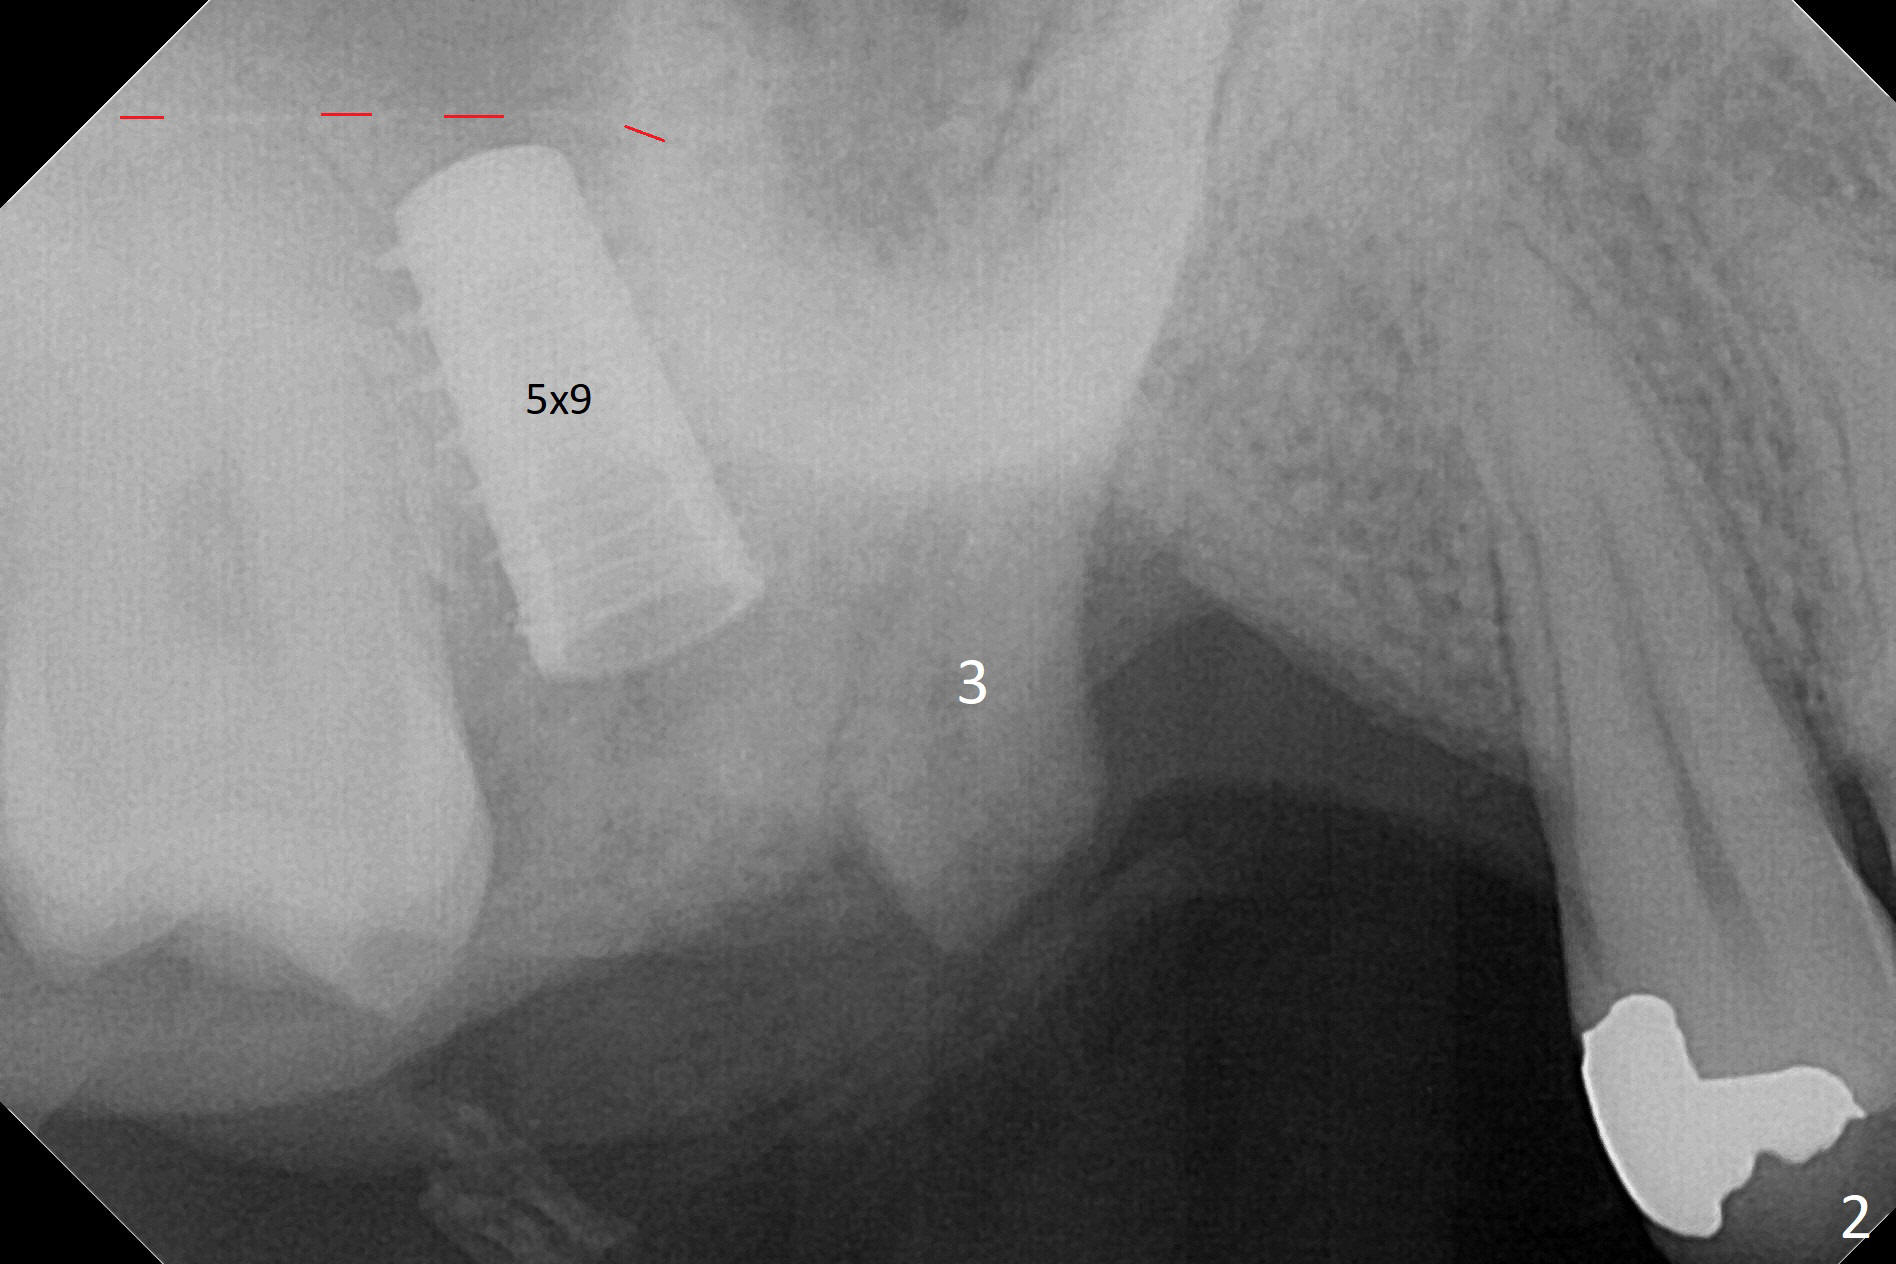

It is difficult to use hard tissue landmark (drill stopper) to make osteotomy in the fresh extraction socket because of socket irregularity and hemorrhage. Once osteotomy is initiated, depth is more reliably controlled with soft tissue landmark (such as gingival margin). This happens in today's case. Without CT information, the osteotomy is established in the buccal slope of the septum of the tooth #2 (after extraction) by using alternatively Magic Sinus Lifter and 4.8 mm Magic Drill (MD). Finally the sinus floor (Fig.1 red dashed line) is lifted after the MD reaches ~16 mm counting from the gingival margin, consistent with preop panoramic X-ray and intraop PA measurement. The 4.5x11 mm dummy implant is close to the impacted 3rd molar (1). Following use of Lindamann bur to move the osteotomy mesially, a 5x9 mm dummy implant is placed away from the 3rd molar (Fig.2 (3: residual root of the 1st molar)). The latter is intentionally not removed in order to maintain osteotomy integrity. A 5x13 mm IBS implant is placed with >50 Ncm; a 6.5x4(4) mm abutment is hand tightened (Fig.3). The remaining large socket is filled with Vera Graft (Fig.4 *). Two months postop, the abutment changes to 6.5x5.7(2) mm without provisional (Fig.5). Nearly 3 months postop, the patient will return for #3 residual root extraction and implant placement with incision (Fig.6). Osteotomy will be initiated in a slope. Prepare surgical round bur for flattening. After placement of a healing abutment, periodontal dressing is to be applied. Take photos to show gingival adaptation to the new abutment without implant exposure at #2.